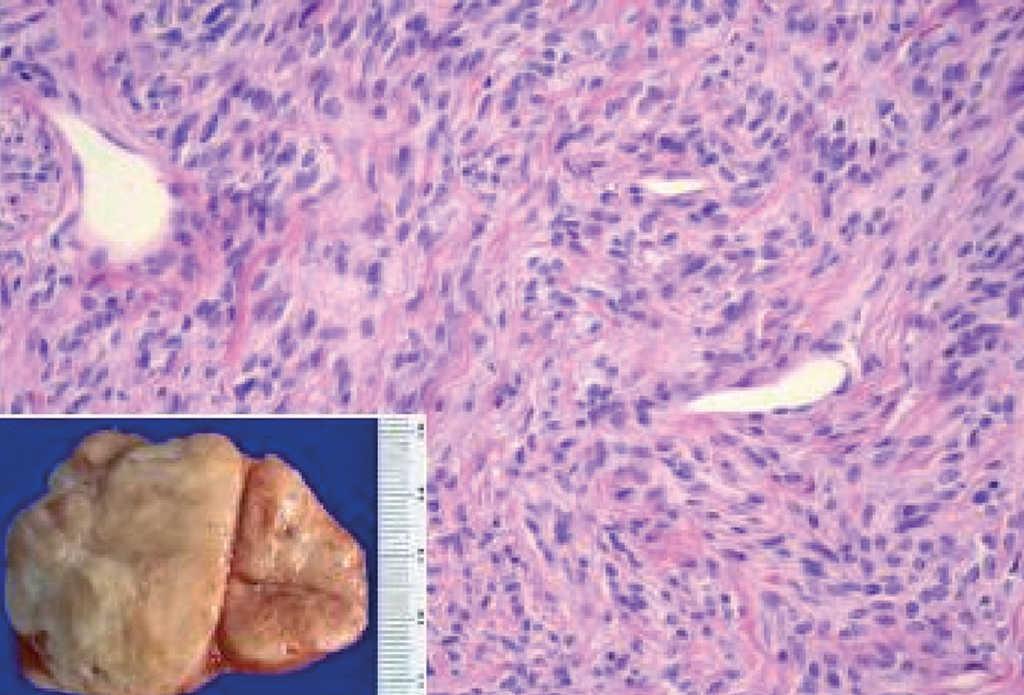

La localización en la pleura visceral fue la más frecuente --se observó en un 70% de los casos (21/30)--, seguida de la intrapulmonar, con un 10% (3/30), y la pleura parietal, con un 16,6% (5/30); un caso (3,3%) presentó nódulos tanto en la región de la pleura visceral como intrapulmonar. En cuanto al número de tumoraciones, el 80% de los pacientes presentó tumoración única (fig. 1) y un 20% tumoraciones múltiples; uno de los casos presentó 55 nódulos. El promedio del tamaño tumoral fue de 7,35 cm (rango: 2-21).

Fig. 1. Macroscopia: tumoración de superficie externa nodular y lisa, de 10 x 9 x 5 cm de ejes mayores y 282 g de peso. La superficie de corte es blanquecina, fasciculada y homogénea. Microscopia: neoplasia fusocelular, que alterna áreas de mayor densidad celular y áreas de escasa densidad celular con abundantes vasos sanguíneos.

Desde el punto de vista histológico, la densidad celular era escasa en el 15%, moderada en el 50% e intensa en el 35%; no presentaba atipia el 55%, ésta era leve en el 30% y moderada en el 15%; mostraba necrosis el 25%, hemorragia el 15% y mitosis de más de 4 por 10 campos el 30%. En el estudio inmuhistoquímico el 100% presentó positividad para vimentina, el 85% para CD34, el 65% para BCL2 y el 40% para CD99 (40%), y en el 100% las queratinas y la proteína S100 fueron negativas (tabla II y fig. 2).